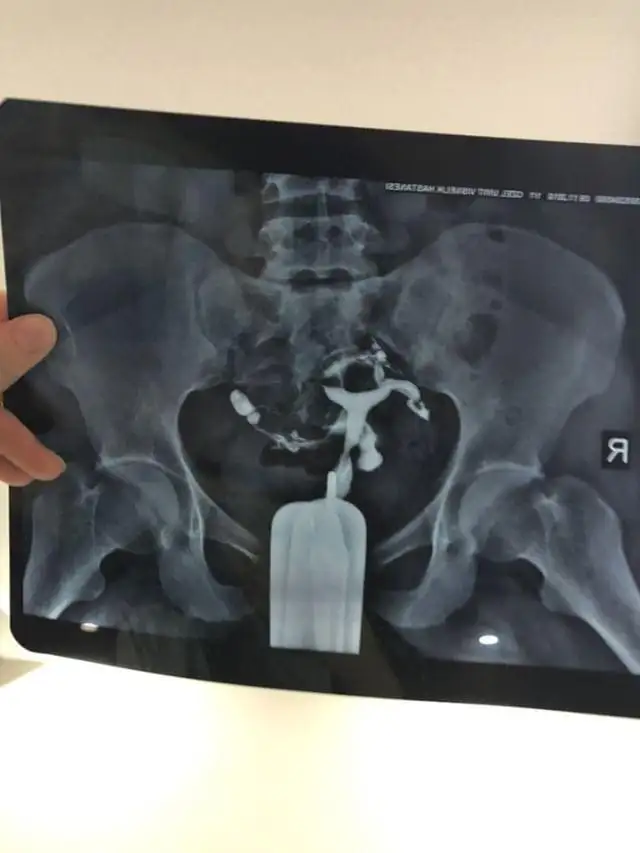

Hsg sonrasi T rahim oldugumu ogrendim. Ayrıca rahimin ileri derecede geriymis. 10 aydir cocuk sahibi olamadik dogal yollarla. Ayrica esimin morfolojisi 1di. Sayisi hareketliligi falan cok dusuktu.